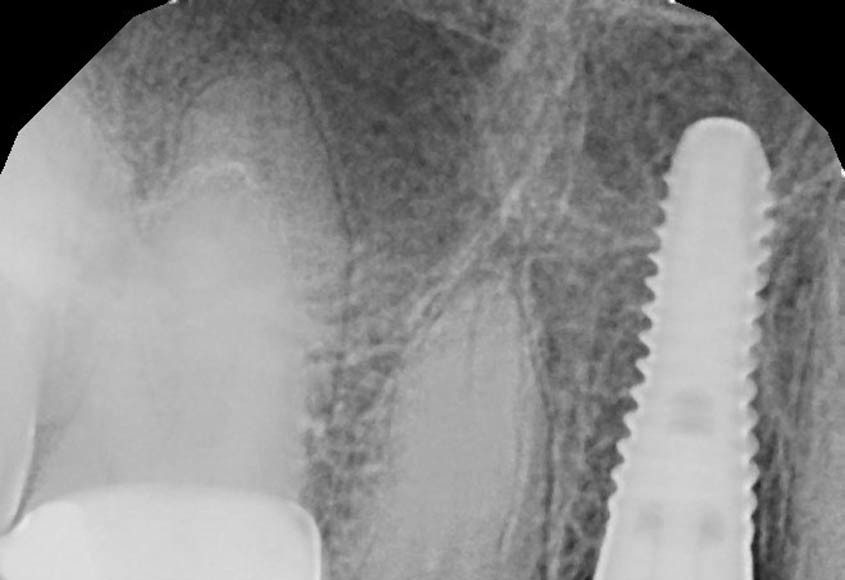

Though not obvious on the x-ray, this patient has fractured his upper right 1st premolar. Treatment plan: Extract tooth, place implant, fabricate an immediate, screw retained, temporary implant crown. Patient will never need to wear a removable partial or go without a tooth.